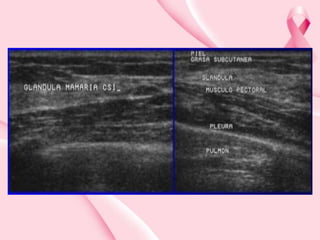

USG normal

Piel

Tejido graso subcutáneo

Parénquima mamario

Tejido graso retromamario

Ligamentos de Cooper

Complejo Pezón-Areola

Seno lactífero